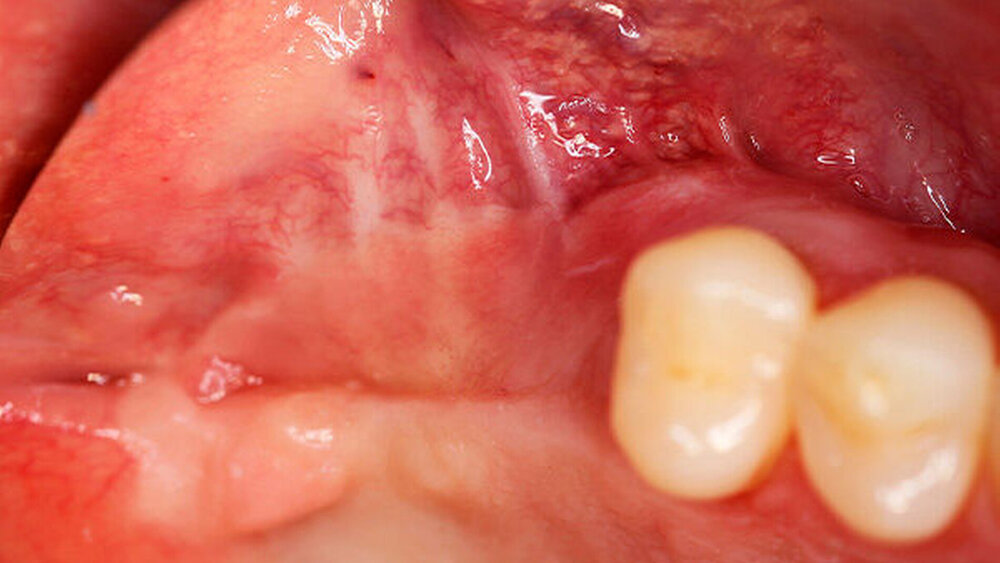

Die Schnittführung wurde nach dem Pillar-Sockel-Design (Blume) vorgenommen. Dabei liegt die Inzision weit im Vestibulum und verbindet zwei vertikale Entlastungsschnitte. Im Gegensatz zu der herkömmlichen krestalen Schnittführung bleibt das Periost über dem augmentierten Bereich damit völlig intakt. Nach der streng subperiostalen Präparation erfolgte die Kontrolle der Passung des CAD/CAM-Blocks. Ein ganz entscheidender Punkt ist, vor jeglichem Kontakt des Blockes mit Blut diesen in steriler Kochsalzlösung und am besten in der PRF-Flüssigkeit zu wässern, sodass sich keine Poren des Blocks mit Blutkoageln verschließen und innerhalb des Blocks ein nicht mit Blut gefüllter Hohlraum bildet. Vor der Befestigung des Blocks wurde die Kompakta des Empfängerbetts mit einer kleinen Kugelfräse mehrfach perforiert um sogenannte Bleeding Points zu setzen, die die Durchblutung des Knochenblocks gewährleisten. Mit zwei Osteosyntheseschrauben mit dem Durchmesser 1,5 mm und der Länge 9 mm wurde der allogene Knochenblock rotationssicher fixiert. Das Augmentat wurde mit einer dünnen Schweinepericard-Membran (Jason membrane, botiss biomaterials GmbH, Vertrieb Straumann) und der PRF-Membran abgedeckt. Der spannungsfreie Wundverschluss erfolgte mit der modifizierten vertikalen Matratzennaht nach Laurrell mit resorbierbarem Nahtmaterial (Vicryl 4.0). Postoperativ wurde ein Oberkiefer-DVT angefertigt. Die Nahtentfernung wurde im Rahmen der Nachsorgeuntersuchung sieben und 14 Tage postoperativ vorgenommen. Nach einer Heilzeit von sechs Monaten erfolgte die Implantation in Lokalanästhesie unter antibiotischer Abschirmung mit 2 g Amoxicillin oral eine Stunde präoperativ. Die Schnittführung erfolgte krestal, und nach subperiostaler Präparation wurde der Knochenblock dargestellt und die Osteosyntheseschrauben wurden entfernt. Danach wurden drei Implantate (Straumann) in den Knochenblock gesetzt und mit 0er-Verschlussschrauben abgedeckt. Die Wundrandadaptation erfolgte mit resorbierbarem Nahtmaterial, das bei der Verlaufskontrolle sieben Tage postoperativ vollständig entfernt wurde. Nach dreimonatiger gedeckter Einheilung wurden die Implantate im Rahmen einer Vestibulumplastik freigelegt. Dafür wurde eine erneute krestale Schnittführung regio 14 bis 17 vorgenommen und ein Splitflap präpariert. Der vestibuläre Wundrand wurde mit Einzelknopfnähten im Vestibulum fixiert. Im Bereich der Implantate wurde der Splitflap perforiert, um die Abdeckschrauben gegen Gingivaformer auszutauschen, und der Bereich des nun freiliegenden Bindegewebes wurde mit einer 3D-vernetzten Kollagenmatrix (mucoderm, botiss biomaterials GmbH, Vertrieb Straumann) abgedeckt. Diese wurde zunächst gewässert, um die Verarbeitung zu erleichtern, und an den Stellen der Gingivaformer gestanzt. Die Nahtentfernung erfolgte neun Tage postoperativ. (Abb. 1a bis 1f).

Ein 29-jähriger Patient stellte sich mit einer massiven Alveolarkammatrophie im rechten Unterkiefer in unserer Praxis vor. Diese lag in langen Jahren der Zahnlosigkeit begründet. Eine Beckenkammaugmentation kam für den Patienten nicht in Betracht. Dennoch wünschte er die Versorgung mit festsitzendem Zahnersatz. Nach ausführlicher Beratung entschied sich auch dieser Patient für eine Augmentation mit einem patientenindividualisierten allogenen CAD/CAM-gefertigten Knochenblock. Die DICOM-Daten des Unterkiefer-DVTs wurde an die Firma Zimmer gesendet, und es erfolgten wie im oben beschriebenen Fall eine virtuelle Planung und das virtuelle Design des allogenen Knochenblocks anhand der geplanten Implantatpositionen. Nach der üblichen Kontrolle und Freigabe des Chirurgen erfolgte die eigentliche Fertigung und Übersendung des Knochenblocks in die Praxis. Die Augmentation erfolgte auch in diesem Fall in Vollnarkose unter antibiotischer Abschirmung perioperativ mit Ampicillin. Die Schnittführung im Unterkiefer unterscheidet sich von der Sockelschnittführung im Oberkiefer aufgrund der Anatomie (N. mentalis). Auch bei diesem Patienten wurde eine tief im Vestibulum liegende bogenförmige Inzi‧sion durchgeführt, jedoch ohne die vertikalen Entlastungen. Nach streng subperiostaler Präparation erfolgte die Darstellung des N. mentalis. Die Vorbereitung des Spenderbetts sowie die Wässerung, Einpassung und Befestigung des allogenen Knochenblocks gestalteten sich wie im Fallbeispiel 1. Die Heilzeit des Knochenblocks dauerte ebenfalls sechs Monate. Zwei Implantate (Straumann) wurden nach krestaler Schnittführung in Lokalanästhesie eingebracht und heilten subgingival binnen drei Monaten ein. Aufgrund des massiven Volumenzuwachses war auch ebenfalls eine Vestibulumplastik im Zuge der Implantatfreilegung notwendig. Das Prozedere verlief ebenfalls wie im Fallbeispiel 1. Das freiliegende Gewebe wurde mit einer Kollagenmatrix abgedeckt. Dadurch konnte die Breite der befestigten Gingiva deutlich verbreitert werden.